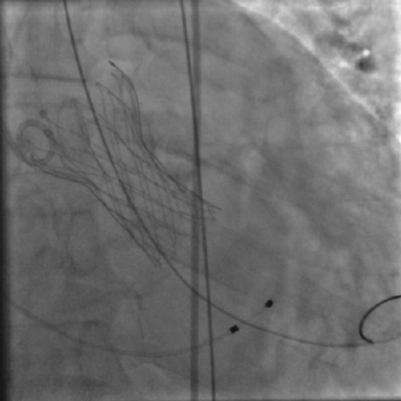

术中影像

主动脉根部造影和冠脉造影+PCI

瓣膜稳定释放和瓣膜释放后左冠显影正常